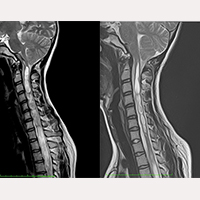

SFT after suboccipital craniectomy (SOC)